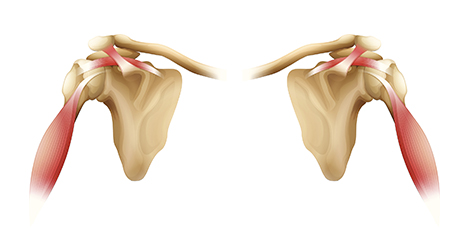

어깨 관절 부위 주요질환

-

오십견

어깨가 얼어버린 것처럼 모든 방향으로 움직일 수 없고, 오랜 기간 통증이 지속

-

회전근개 손상

어깨회전근 힘줄에 염증이 생긴 질환

-

이두근 건염

상완이두근의 힘줄에 염증이 생기는 질환